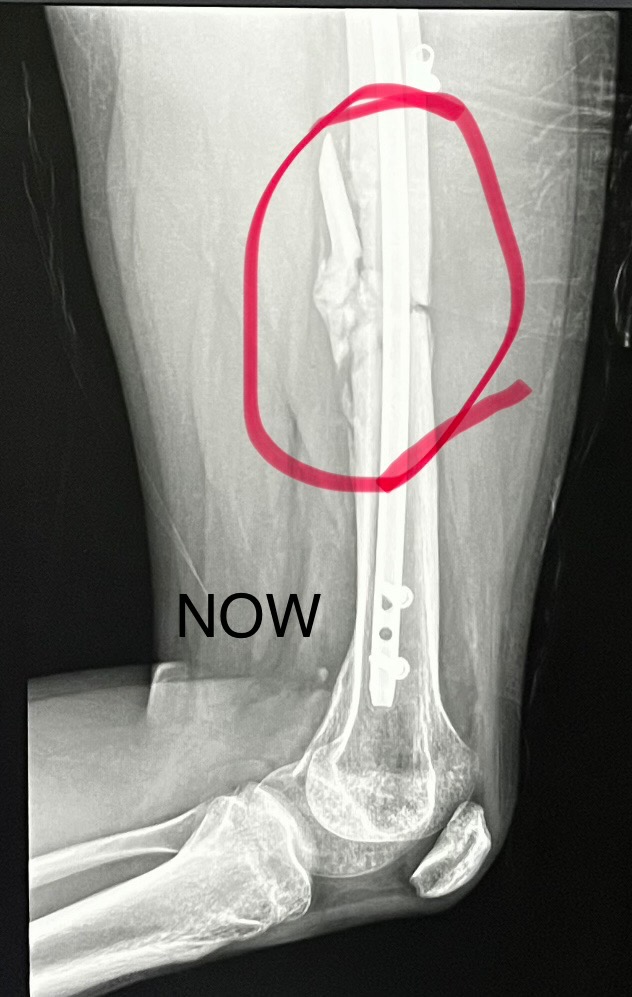

Leo’s injuries are severe—he shattered his left leg and required emergency surgery to insert a rod with three screws. The doctors have told us that two pieces of his bone may never fully heal or connect to the rod, making his recovery uncertain and challenging. Leo now faces a long road of physical therapy, ongoing doctor visits, and significant medical expenses. He will need help with living costs while he focuses on healing and regaining his strength.